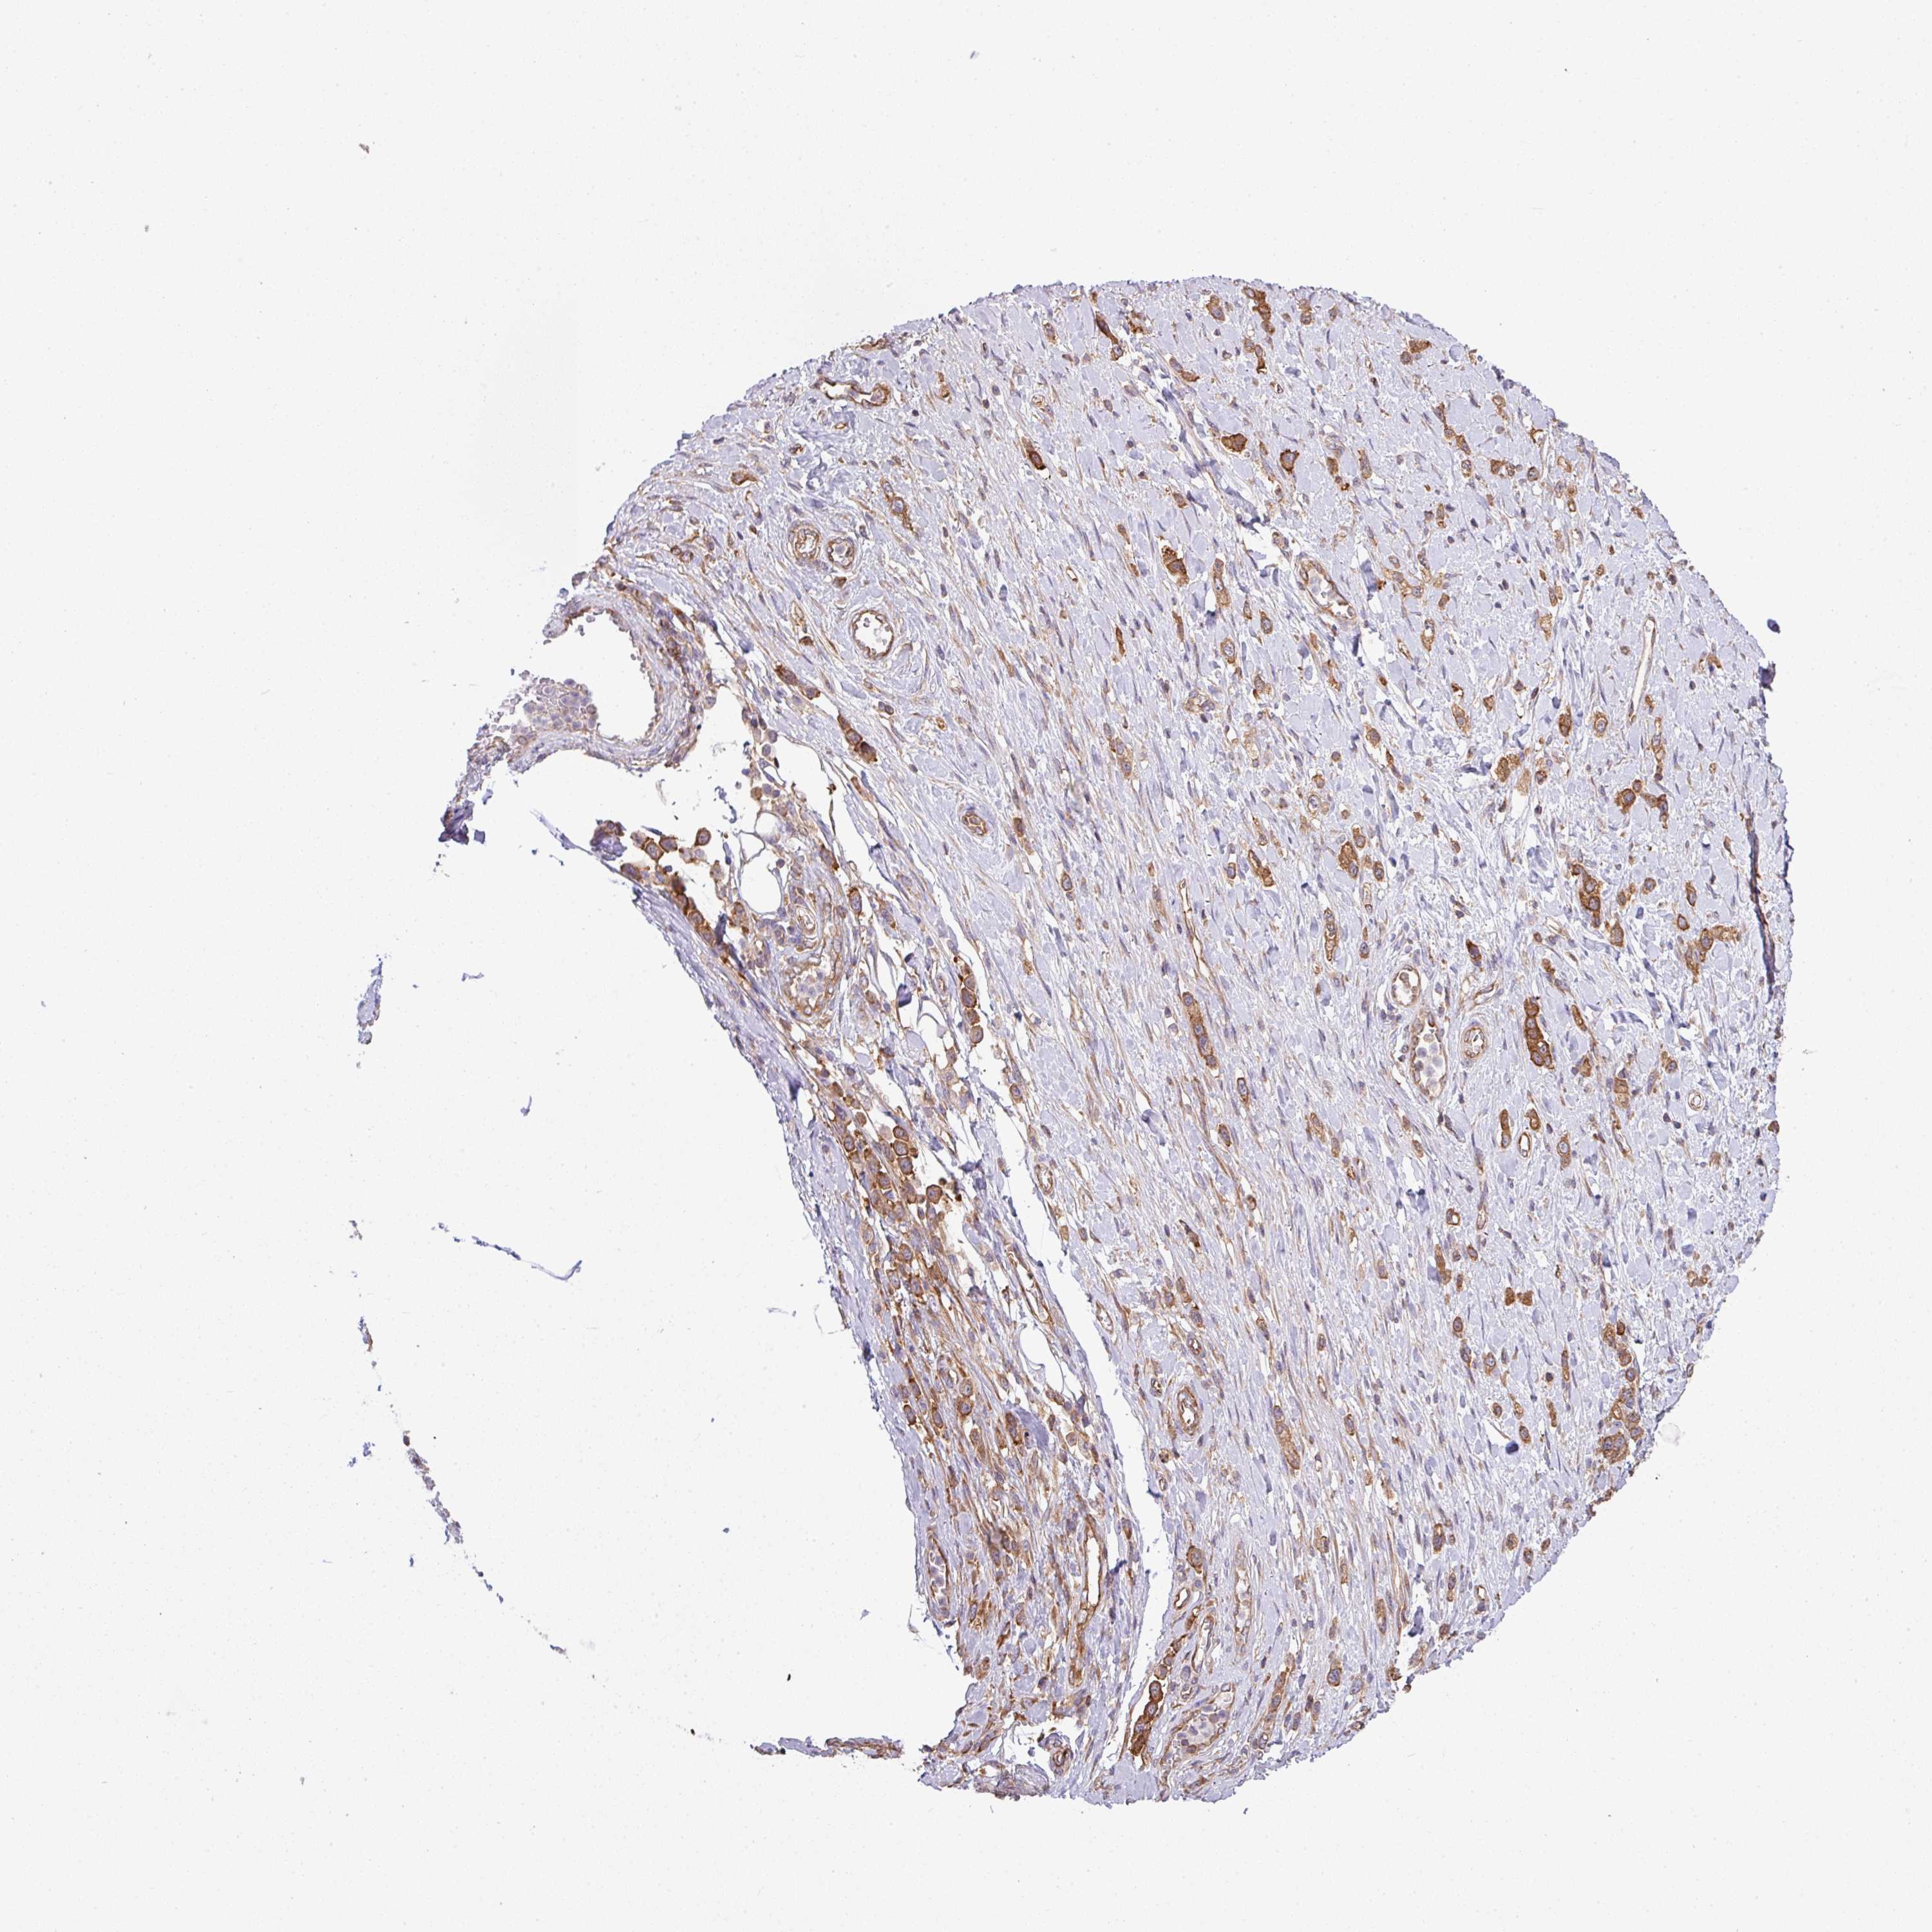

STOMACH CANCER - Protein expressioni

A mouse-over function shows sample information and annotation data. Click on an image to view it in a full screen mode. Samples can be filtered based on level of antibody staining by selecting one or several of the following categories: high, medium, low and not detected. The assay and annotation is described here.

Antibody stainingi

Antibody staining in the annotated cell types in the current human tissue is reported as not detected, low, medium, or high, based on conventional immunohistochemistry profiling in selected tissues. This score is based on the combination of the staining intensity and fraction of stained cells.

Each image is clickable and will lead to virtual microscopy that enables deeper exploration of all samples and also displays staining intensity scores, fraction scores and subcellular localization as well as patient and tissue information for each sample.

Antibody HPA050977

Staining

High

Medium

Low

Not detected

Intensity

Strong

Moderate

Weak

Negative

Quantity

>75%

75%-25%

<25%

None

Location

Nuclear

Cytoplasmic/membranous

Cytoplasmic/membranous,nuclear

Adenocarcinoma, NOS